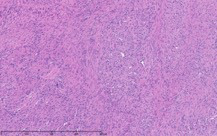

The patient was a 40-year-old white woman with a medical history significant for asthma, obstructive sleep apnea, and Down syndrome and who presented with dyspnea and fevers up to 102°F. She had recently completed an outpatient course of azithromycin, but she presented to an outside hospital for worsening shortness of breath despite this therapy. At the outside hospital, a computed tomography (CT) scan of the chest revealed a 3.7-cm heterogeneously enhancing mass that obstructed the bronchus intermedius with right middle and lower lobe consolidation (Figure 1a). The coronal thoracic CT scan demonstrated right middle and lower lobes that were atelectatic and consolidated with extensive and diffuse secondary mucous plugging (Figure 1b). Laboratory examination results at this time were significant for a white blood cell count 16.5x103/µL, sodium level of 133 mEq/L, potassium level of 3.2 mEq/L, serum creatinine level of 0.54 mg/dL, calcium level of 11.7 mg/dL, and lactic acid level of 2 mmol/L. She was transferred to the presenting institution for further evaluation and management.